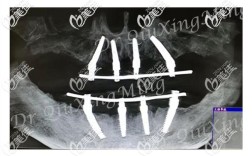

下牙全部缺失(即无牙颌)进行种植牙修复是一个非常复杂但效果显著的解决方案,能够极大地恢复咀嚼功能、美观和自信心,以下是关于下颌全口种植牙的详细说明:🦷一、核心概念:种植体支持的固定修复目标:通过在下颌骨内植入多颗种植体,在其上部安装一个...

牙槽骨萎缩(也称为牙槽骨吸收或骨量不足)是全口种植牙面临的主要挑战之一,但幸运的是,现代口腔种植技术已经发展出多种有效的方法来克服这个问题,实现成功的全口种植修复,🦷核心问题:牙槽骨萎缩为什么是挑战?骨量不足:牙齿缺失后,缺乏功能刺激,...

看到您面临“牙周严重全口牙种植”的问题,我能感受到您此刻的困扰和迫切希望恢复咀嚼功能的愿望,严重牙周炎导致全口牙齿缺失或松动,确实给生活带来了巨大挑战,但请放心,通过系统性的治疗,重建健康美观的牙齿是完全可能的,虽然过程相对复杂,但现代牙科...

是的,牙全部掉了(全口无牙)是可以进行种植牙修复的,而且这已经成为一种非常成熟和受欢迎的解决方案,这比单颗或少数几颗牙的种植要复杂得多,需要更全面的评估和更复杂的治疗方案,以下是关于全口种植牙的关键信息:🦷1.可行性:绝对可行技术成熟:...